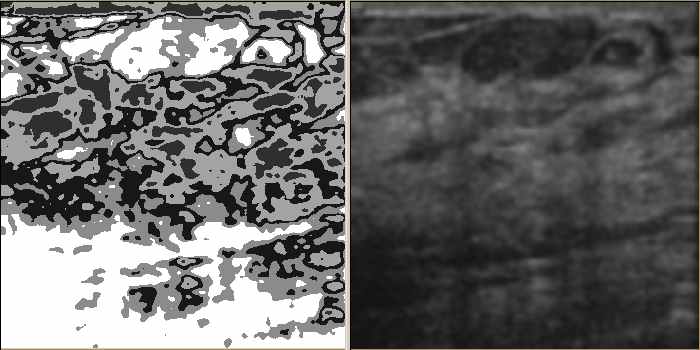

Computer-Aided Detection in Ultrasound: The current method of detection and analysis of suspicious areas is based on manual inspection of the acquired images. It is subjective and error-prone. Our technology not only can view and display comprehensively (enhanced view on the left and traditional view on the right), but can detect, quantify and search images too.

Quantification and Scoring of suspicious area: Previously detected suspicious areas are automatically detected and quantified. They can then be compared to one marked by radiologist (accuracy test) and numerically scored to the level of suspicion.